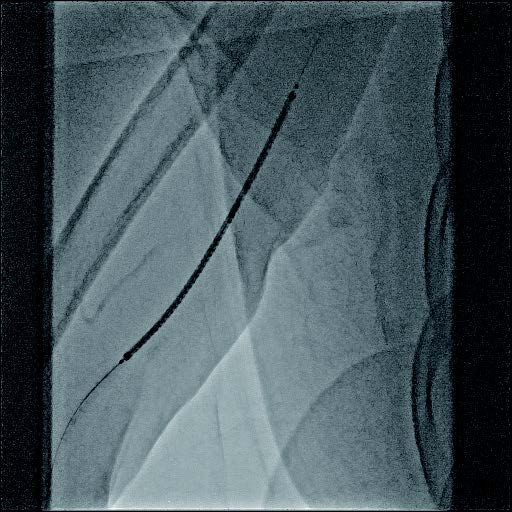

- シース:7 Fr シース

- ガイドワイヤー:0.018 inch (サポートタイプ)

- PTA バルーンカテーテル:径6 mm×長100 mm

- ステントグラフト:バイアバーン® ステントグラフト 径7 mm×長100 mm

バイアバーン® ステントグラフト留置の手技については、当施設では概ね毎回同じ手技を実施している。ステントグラフトの長さについては病変に依存するが、径については6 mmの人工血管に対して、7 mmのバイアバーン® ステントグラフトを留置している。

静脈とはいえ、透析患者においては硬化性変化が強い病変が多く、indentation を残さずに pre dilatation をかけておくことが重要と考えられる。そこで、径7 mmのバイアバーン® ステントグラフト留置前に、径6 mmの高耐圧バルーンにてしっかり拡張し、indentationを残さないことを確認した。バイアバーン® ステントグラフト留置後もバルーンでステント内、特に人工血管とのオーバーラップ部位にしっかり圧をかけて後拡張を行っている。

また、バイアバーン® ステントグラフトは、位置決めをした後の留置時に移動する事象は自施設で行った症例ではほとんど認めていないが、展開時のstabilityを保つため0.018 inchのサポートワイヤーを用いることが多い。当患者においても、上記手技を行い良好なinitial successを得られた。他症例もほぼ同一の手技で行っているがサイズなどで問題になった症例は、本稿の執筆時点では経験していない。